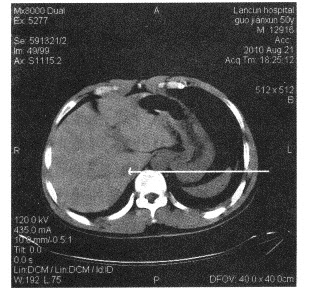

下面上腹部断层图像中箭头所指为()

A:腹主动脉

B:门静脉

C:下腔静脉

D:肝静脉

E:胆总管